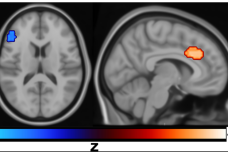

《自然·通讯》:焦虑的大脑功能乱窜

• 互联网数据资讯网-199IT

• 2023年11月19日

• 作者 DinK

1688030867-4184-iam5TqSCrYFPZHn3BvJkwD7DicdQ.png